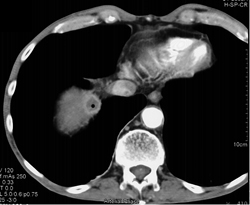

Focal Nodular Hyperplasia (FNH)